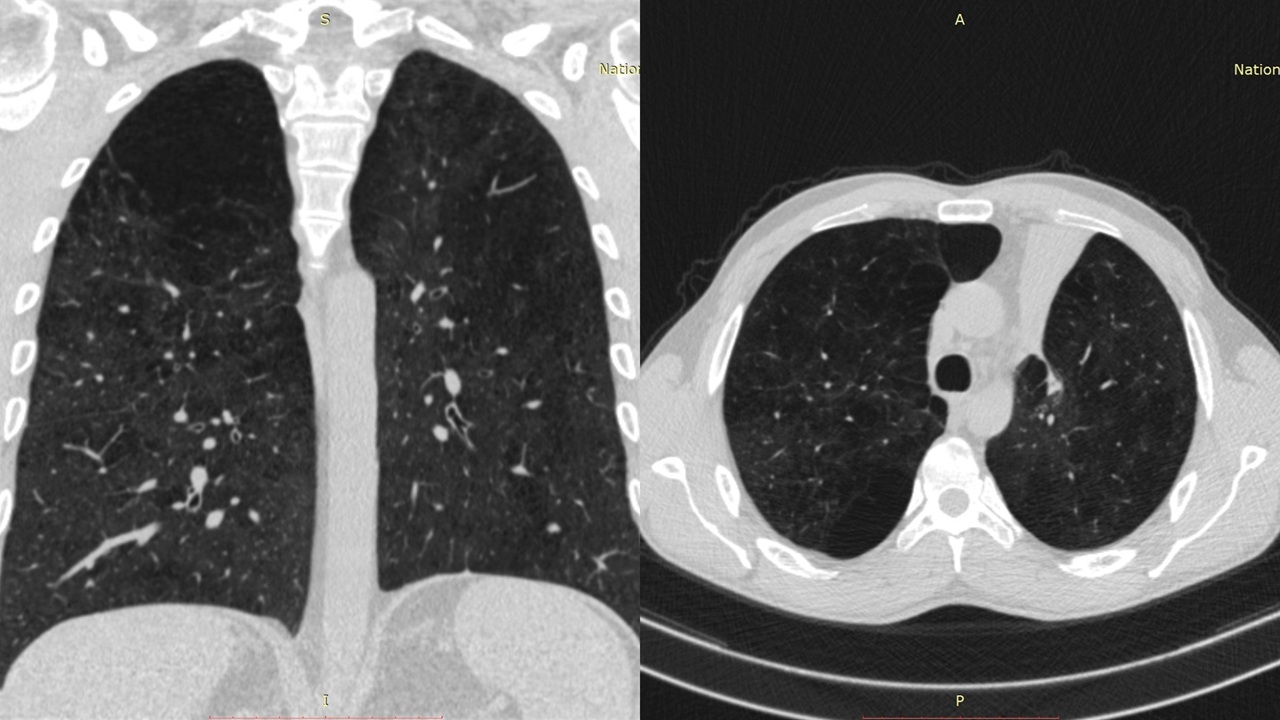

პაციენტი 42 წ მამაკაცი. აქტიური მწეველი. თავს ავად გრძნობს რამოდენიმე თვეა. ჩივილები: ძლიერი ქოშინი ფიზიკურ დატვირთვაზე, ჰაერის უკმარისობა, საერთო სისუსტე. გულმკერდის კტ კვლევით – ორივე ფილტვის ზედა წილებში გაიშვიათებული ფილტვის ქსოვილი, გიგანტური ბულები 10-14 სმ ზომის (16 იან 2020 წ). ბოდიპლეტიზმოგრაფიით – RV (Pleth) 3.90 ლ (Normal Range 1.14-2.49 ლ) (18 თებ 2020 წ). 2020 წლის 18 თებერვალს მარცხენა ფილტვის მოცულობის შემცირების მიზნით პაციენტს ჩაუტარდა რიგიდული ბრონქოსკოპია – სარქვლოვანი ბრონქობლოკაცია. ზოგადი გაუტკივარების ქვეშ ტრაქეაში შეყვანილი იყო Friedel-ის რიგიდული ბრონქოსკოპი. გამოყენებული იყო ტუბუსი N13. მარცხენა ზ/წ ბრონქის სანათურში მოთავსდა სარქვლოვანი ბრონქობლოკატორი N15. მანიპულაციიდან 3 თვის შემდეგ საკონტროლო გულმკერდის კტ კვლევით – მარცხენა ზედა წილში გიგანტური ბულა აღარ ფიქსირდება, ბოდიპლეტიზმოგრაფიით – RV (Pleth) 2.44 ლ (Normal Range 1.14-2.49 ლ) (25 მარ 2020 წ). გულმკერდის კტ კვლევით დადებითი დინამიკა შენარჩუნდა 9 და 12 თვის შემდეგ.